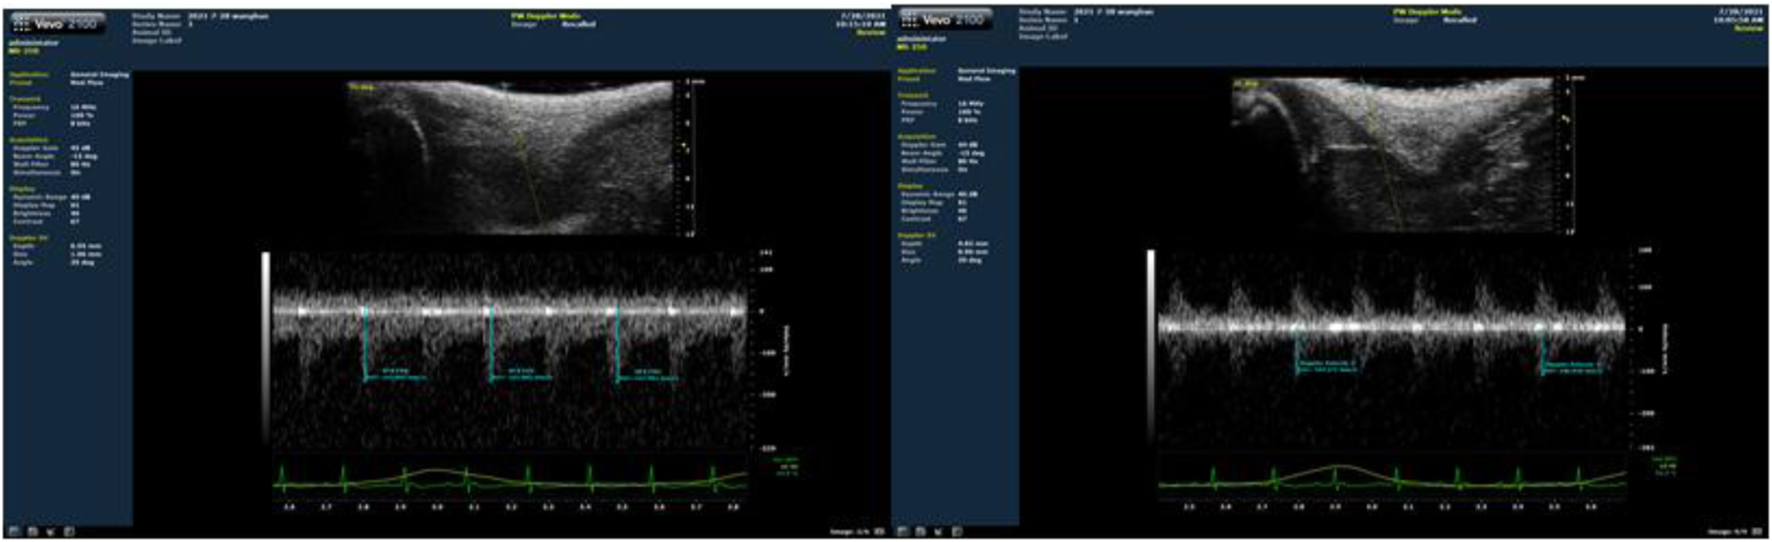

Figure 1. Rat weight-bearing ladder climbing training [left (A)], Color ultrasound detection of small animals [right (B)].

Blood flow restriction intervention method

As shown in Figure 1B, blood flow velocity was detected at the root of the rat’s lower thigh using a small-animal-specific high-frequency color ultrasound (Visual Sonics Co., Toronto, Canada), and rubber bands of appropriate lengths were selected to encircle the thigh roots of the lower limbs of rats to ensure that the blood flow velocity was restricted to 30%–40% (Figure 2), Remember the length of the rubber bands used for each rat, which refers to the length of the restriction band that should be applied in the subsequent training sessions. During training, binding was performed at 1-min intervals, and blood flow restriction was lifted and blood flow reperfusion was performed (Tan et al., 2023). After rest, the area was bound again with rubber bands. In order to minimize the error of the rat’s lower limb size with growth changes and to ensure that the blood flow restriction was within the specified range, ultrasonic probing was performed every 3 weeks, and the length of the rubber bands was appropriately adjusted during training. In addition, the experimenters were trained to recognize signs of excessive blood flow restriction (e.g., unusual movement or skin discoloration) and to stop the intervention as soon as these signs appeared and make appropriate adjustments.

Figure 2. Ultrasound detection of the proportion of blood flow restriction (The left picture is before blood flow restriction, and the right picture is after restriction).